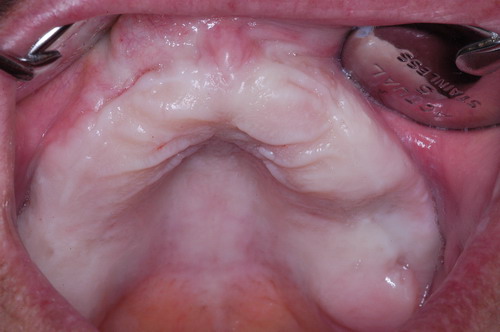

EL USO DEL ARCO GÓTICO DE GYSI , MEDIANTE UNA BÓVEDA PALATINA Y UN APOYO CENTRAL ÚNICO (BO PA YA CU) , EN LA UBICACIÓN DE LA RELACIÓN CÉNTRICA EN UN CASO DE GRAN LAXITUD TENDINOSA CAPSULAR. EL PACIENTE SE PRESENTA A CONSULTA CON UNA EDENTACIÓN PARCIAL, Y GRADO DE MOVILIDAD EXTREMO EN TODAS SUS PIEZAS REMANENTES. SE ESTUDIA EL CASO RADIOGRÁFICA Y CLÍNICAMENTE , Y EL PACIENTE RELATA ESTAR EN ESE ESTADO DESDE HACE MUCHO AÑOS. AL MANIPULAR LA MANDÍBULA EN UN INTENTO DE CONOCER EL ESTADO MUSCULAR DEL SISTEMA, SE OBSERVA UNA GRAN LABILIDAD TENDINOSA CAPSULAR QUE SE MANIFIESTA EN UNA HIPER LAXITUD EN LOS MOVIMIENTOS MANUALMENTE INDUCIDOS DE AMBOS CÓNDILOS DENTRO DE LA CAVIDAD. SE TOMAN IMPRESIONES Y SE MONTA EN UN ARTICULADOR SEMI AJUSTABLE , CORTANDO EN EL YESO LAS PIEZAS QUE SERÁN EXTIRPADAS , CONSERVANDO UNICAMENTE , AMBOS PRIMEROS PREMOLARES INFERIORES , QUE SERÁN UTILIZADOS PARA RETENER MEDIANTE RETENEDORES ELÁSTICOS LA PRÓTESIS INFERIOR , EN LA PRESUNCIÓN DE LA HIPERMOVILIDAD A QUE SERÁ SOMETIDA DADO QUE EN LA GRAN REABSORCIÓN ÓSEA , ES FRECUENTE EL ACERCAMIENTO DE TODAS LAS INSERCIONES MUSCULARES A LA PORCIÓN SUPERIOR DEL REBORDE ÓSEO , LO QUE ATENTARÁ CONTRA LA ESTABILIDAD DE DICHA PRÓTESIS PROVISIONAL. EN UNA PRIMERA SESIÓN CLÍNICO QUIRÚRGICA , SE EXODONCIA TODO EL SECTOR INCISIVO Y CANINO INFERIOR , Y AL OBSERVAR EL REMANENTE ÓSEO CANINO DE AMBOS LADOS , SE IMPLANTA EN FORMA INMEDIATA . TANSCURRIDOS DOS MESES , DONDE LA CICATRIZACIÓN ES ADECUADA , Y LA DINÁMICA MANDIBULAR ACEPTABLE , SE PROCEDE A LA ETAPA QUIRÚRGICA IMPLANTARIA MEDIANTE IMPLANTES SEMI SUMERGIDOS, CON ALGUNAS ZONAS DE REGENERCIÓN ÓSEA GUIADA FIG17 FIG18 FIG19 FIG26 DURANTE LA ETAPA DE CICATRIZACIÓN DE ESTE NUEVO ABORDAJE QUIRÚRGICO , SE ENDODONCIAN AMBOS PREMOLARES INFERIORES CONSERVADOS , LOS QUE EN UN FUTURO , CUANDO YA NO SIRVAN PARA RETENER LA PRÓTESIS REMOVIBLE PROVISORIA INFERIOR , SERÁN CORTADOS COMO RESERVA DE CAPITAL ÓSEO O BIEN COMO ELEMENTO RETENEDOR ANTE CUALQUIER TIPO DE INCIDENCIA IMPLANTARIA. ABORDAMOS LA ETAPA PRIMARIA PROTÉTICA , UNA VEZ TRANSCURRIDOS TRES MESES, MEDIANTE LA UTILIZACIÓN DE CUBETAS INDIVIDUALES , A LAS QUE REALIZAMOS UN RECORTE MUSCULAR EN BASE A STENS VERDE , COMO SI DE UNA PRÓTESIS COMPLETA SE TRATARA. DE ESE MONTAJE OBTENEMOS DOS RODETES DE METACRILATO , PERFECTAMENTE ADAPTADOS A LOS MODELOS FUNCIONALES , A LOS QUE LES OTORGAMOS LA PLANIMETRÍA DERIVADA DEL PARALELISMO CON EL PLANO DE FRANKFURT , Y UNA ALTURA (DV) QUE RESULTA DE LOS MÉTODOS MÉTRICOS DE DIMENSIÓN VERTICAL… Y QUE NOS SERVIRAN ADEMÁS DE TOMAR UNA NUEVA IMPRESIÓN FUNCIONAL MEDIANTE RECORTE MUSCULAR , PARA ADAPTAR UN DISPOSITIVO CONSISENTE EN UNA BÓVEDA PALATINA SUPERIOR , Y UN TORNILLO CENTRAL INFERIOR , LOS QUE DESPUÉS DE UN ENTRENAMIENTO ADECUADO DEL ENFERMO , NOS PERMITIRÁ REPRODUCIR EN EL BÓVEDA , EL ARCO GÓTICO DE GYSI , ENCONTRANDO DE ESTA MANERA LA OCLUSIÓN EN RELACIÓN CÉNTRICA. ACTUALMENTE ESTE MÉTODO HA SIDO RECREADO MEDIANTE LA DENOMINACIÓN DE: FIG50 FIG51 FIG52 OBTENIDO EL DIBUJO DEL ARCO GÓTICO , INSINUAMOS EN EL VÉRTICE DEL MISMO UNA PERFORACIÓN QUE FIJARÁ LA PUNTA DEL TORNILLO EN ESA POSICIÓN: RELACIÓN CÉNTICA FIG55 FIG56 FIG57 CON ESTOS PARÁMETROS SE CONSTRUYEN DOS SOBREDENTADURAS ABROCHADAS EN RÓTULAS SUPRA IMPLANTES , QUE LE OTORGAN FIJACIÓN SUFICIENTE , DANDO A LA OCLUSIÓN TODOS LOS ELEMENTOS DE UNA: OCLUSIÓN MUTUAMENTE COMPARTIDA, REFERENCIA II CON UN ESQUEMA OCLUSAL DE : FUNCIÓN DE GRUPO BILATERAL POSTERIOR DE ACCIÓN CANINA DESPUÉS DE LAS REVISIONES PERTINENTES A LA SEMANA , EL MES Y LOS SEIS MESES DE TERMINADA LA REHABILITACIÓN , SE CITA AL ENFERMO PARA UN NUEVO CONTROL AL AÑO Y MEDIO Y SE OBSERVA UNA PERFECTA SITUACIÓN TISULAR , CLINICA Y RADIOGRAFICAMENTE CONTROLADA , Y ADEMÁS LA PERMANENCIA DEL MISMO ESQUEMA OCLUSAL OTORGADO DESDE EL PRINCIPIO. SE CONTROLA RADIOGRAFICAMENTE Y SE DA EL ALTA DEFINITIVA RECOMENDANDO EL CONTROL DOS VECES AL AÑO. REFERENCIAS: I : II. : III: